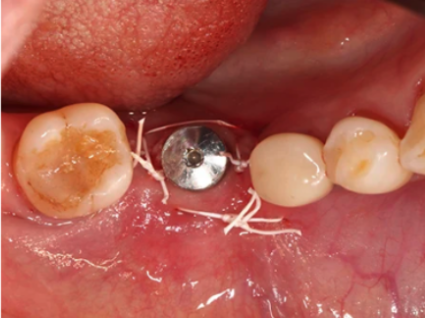

症例①:奥歯・通常のインプラント埋入

※上記画像は、インプラント治療の症例になります。

| 治療内容 | 右下第1大臼歯(6)インプラント埋入 |

| 費用 | 462,000円(税込) |

| 治療期間 | 約2ヶ月 |

| リスク | 下歯槽神経の損傷、オトガイ下動脈の損傷、術後の感染 |

| 副作用 | 術後の痛みと腫れと内出血が出る可能性があります |